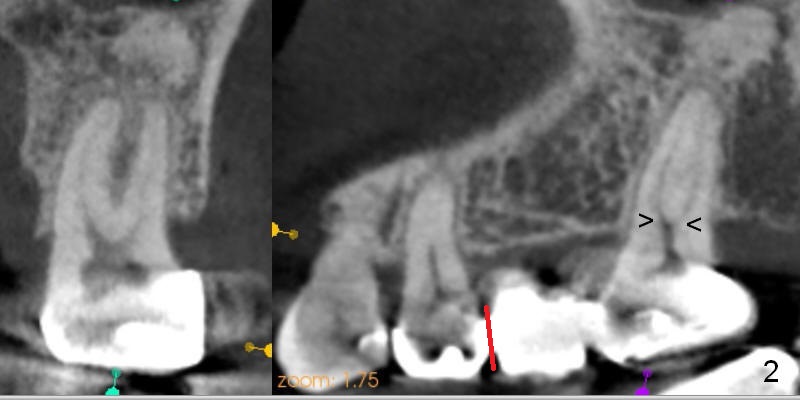

A 47-year-old woman complains of chewing pain at #15 after #30,31 implant placement. It appears that there is mesial open margin (caries, Fig.1). The bridge is to be sectioned at the junction between #13 and 14 (Fig.2 red line). It is expected that #14 and 15 units will fall out by themselves. Examine and remove caries at #15. Conduct pulpal test and start RCT if there is time and necessity. There is one common buccal orifice with two canals (Fig.2 arrowheads). Be prepared for provisional for #15. An implant will be placed at #14.